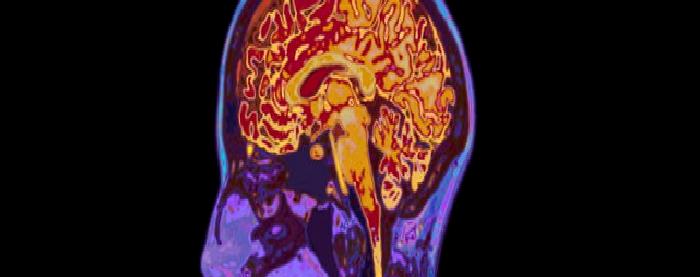

Beyin vücudun en fazla kanlanan organlarından biridir. Vücudun ağrılığının sadece 1/40 oluşturmasına rağmen kan dolaşımın %15 beyinden geçer. Bu kadar yüksek akım beyinin normal çalışmasını sağlar. Fakat aynı zamanda beyini besleyen damarlar vücudun diğer damarlarına göre daha fazla stres altında kalır. Öte yandan beyin kafa içince kapalı bir ortamda yer almaktadır. Kanamaya bağlı hacim arıtışı kafa içindeki basıncın artmasına neden olup beyini negatif yönde etkiler. Dolayısıyla beyin kanamaya en çok meyilli olup kanamaya en az dayanabilen organdır.